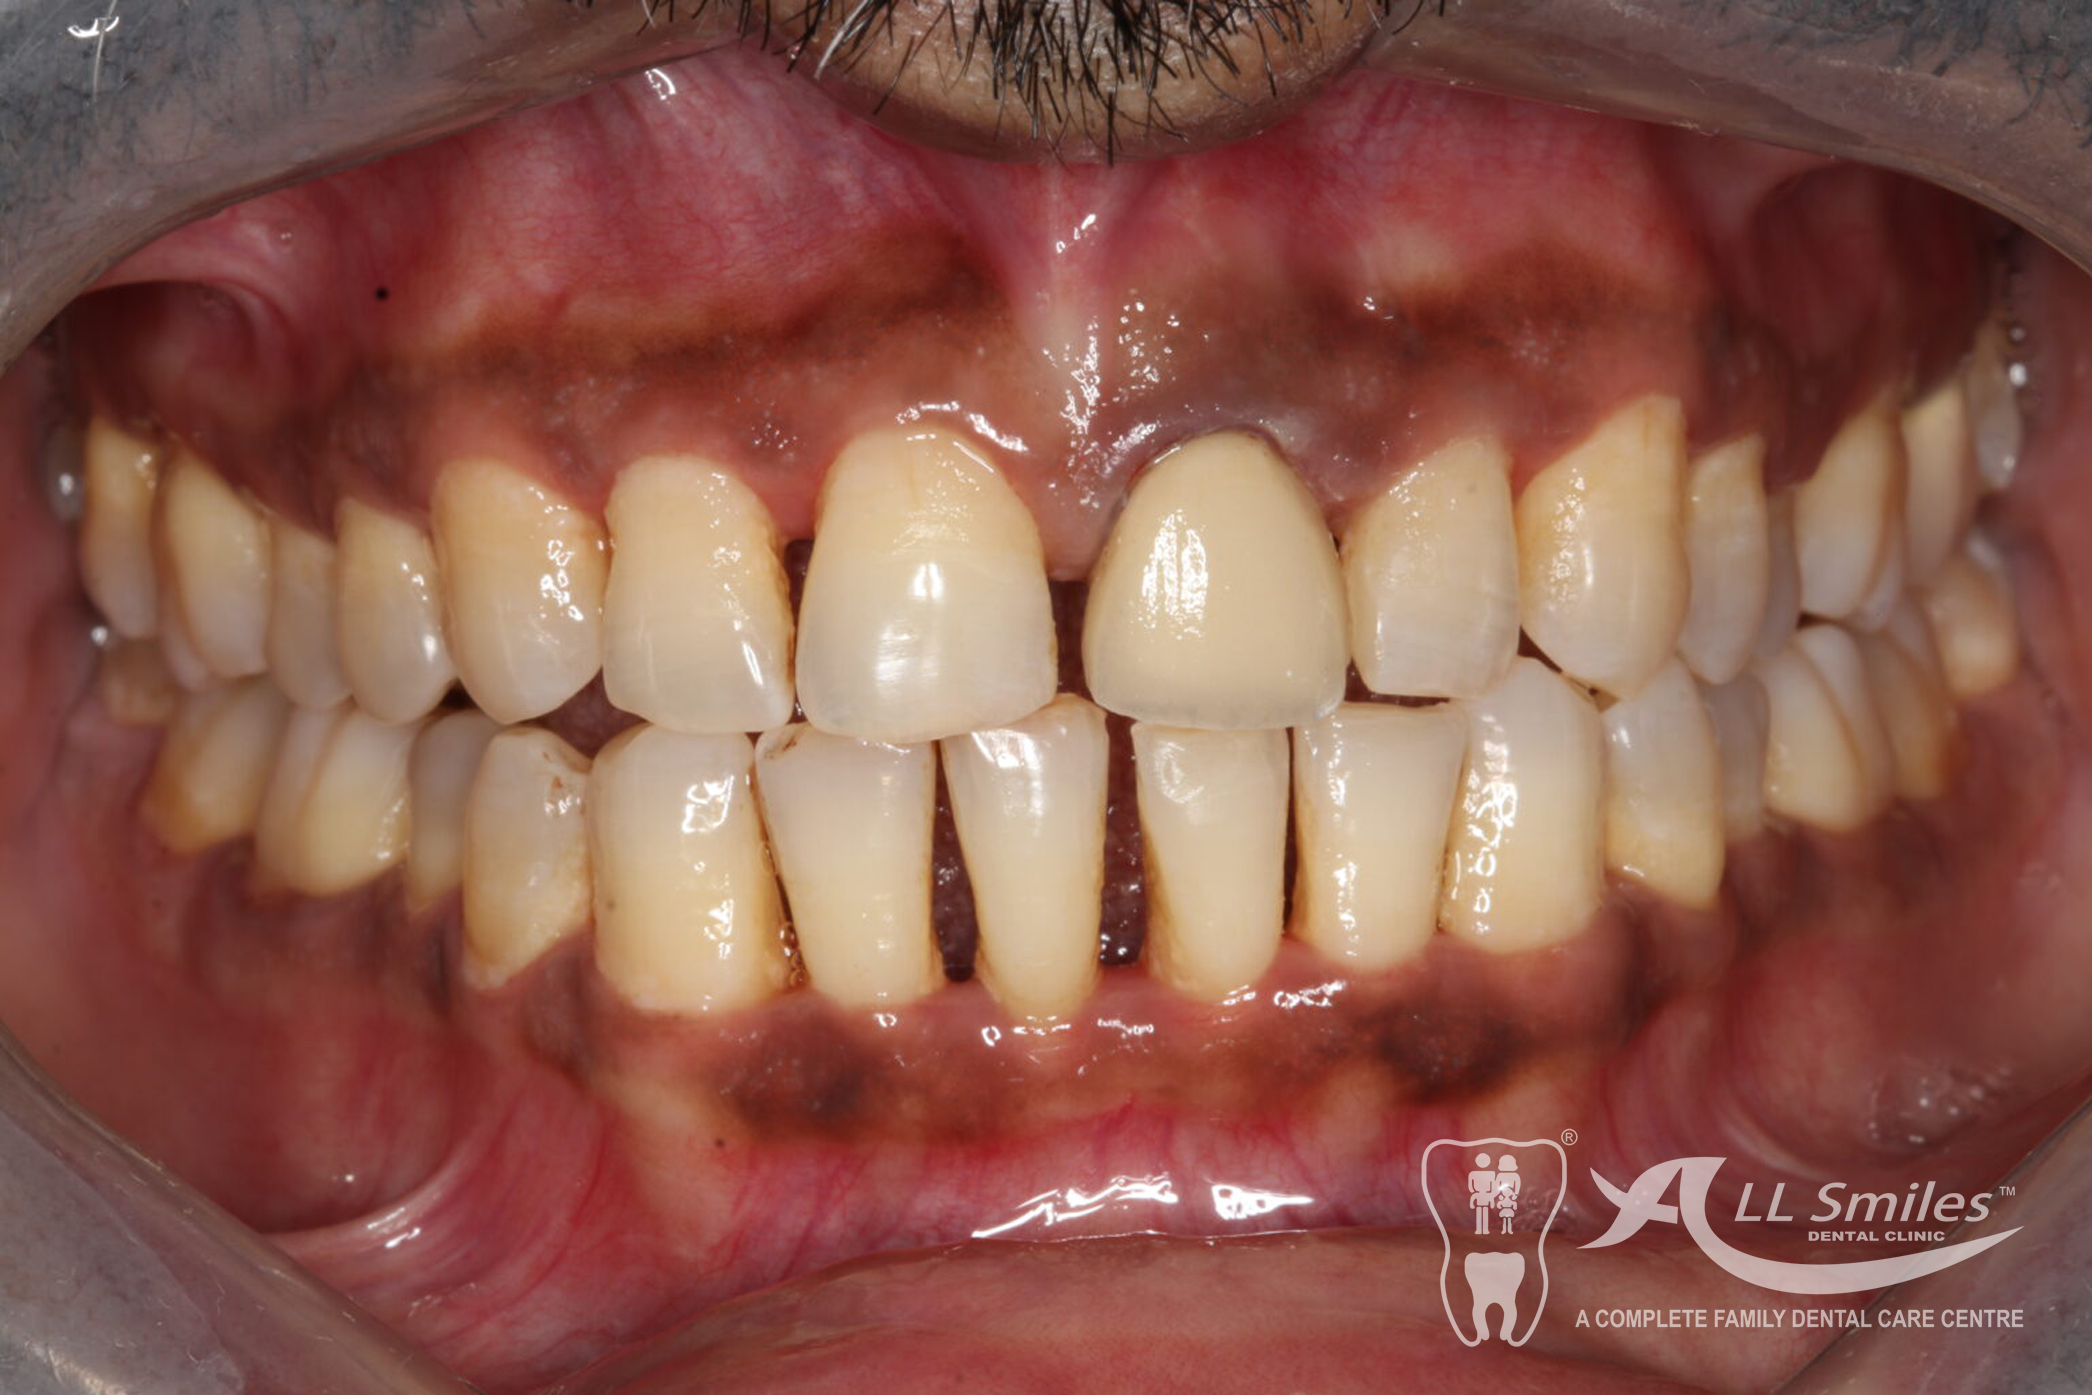

Crowns & Bridges Gallery